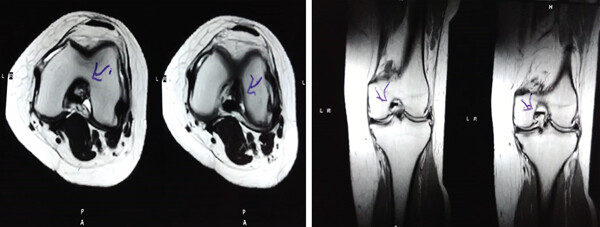

MRI:治療前后的MRI結(jié)果

治療前后的MRI結(jié)果

治療前 MRI 顯示內(nèi)側(cè)和外側(cè)半月板后角 III 級(jí)撕裂。

治療后MRI檢查顯示內(nèi)側(cè)和外側(cè)半月板后角撕裂有所改善?;颊甙Y狀改善,日常生活活動(dòng)能力增強(qiáng)。

治療后MRI檢查顯示內(nèi)側(cè)和外側(cè)半月板后角撕裂有所改善

結(jié)論:間充質(zhì)干細(xì)胞治療后,MRI檢查顯示內(nèi)側(cè)和外側(cè)半月板后角撕裂有所改善 ,關(guān)節(jié)功能也有改善,未出現(xiàn)嚴(yán)重不良事件。可以達(dá)到干細(xì)胞治療半月板損傷短期療效的目標(biāo)。